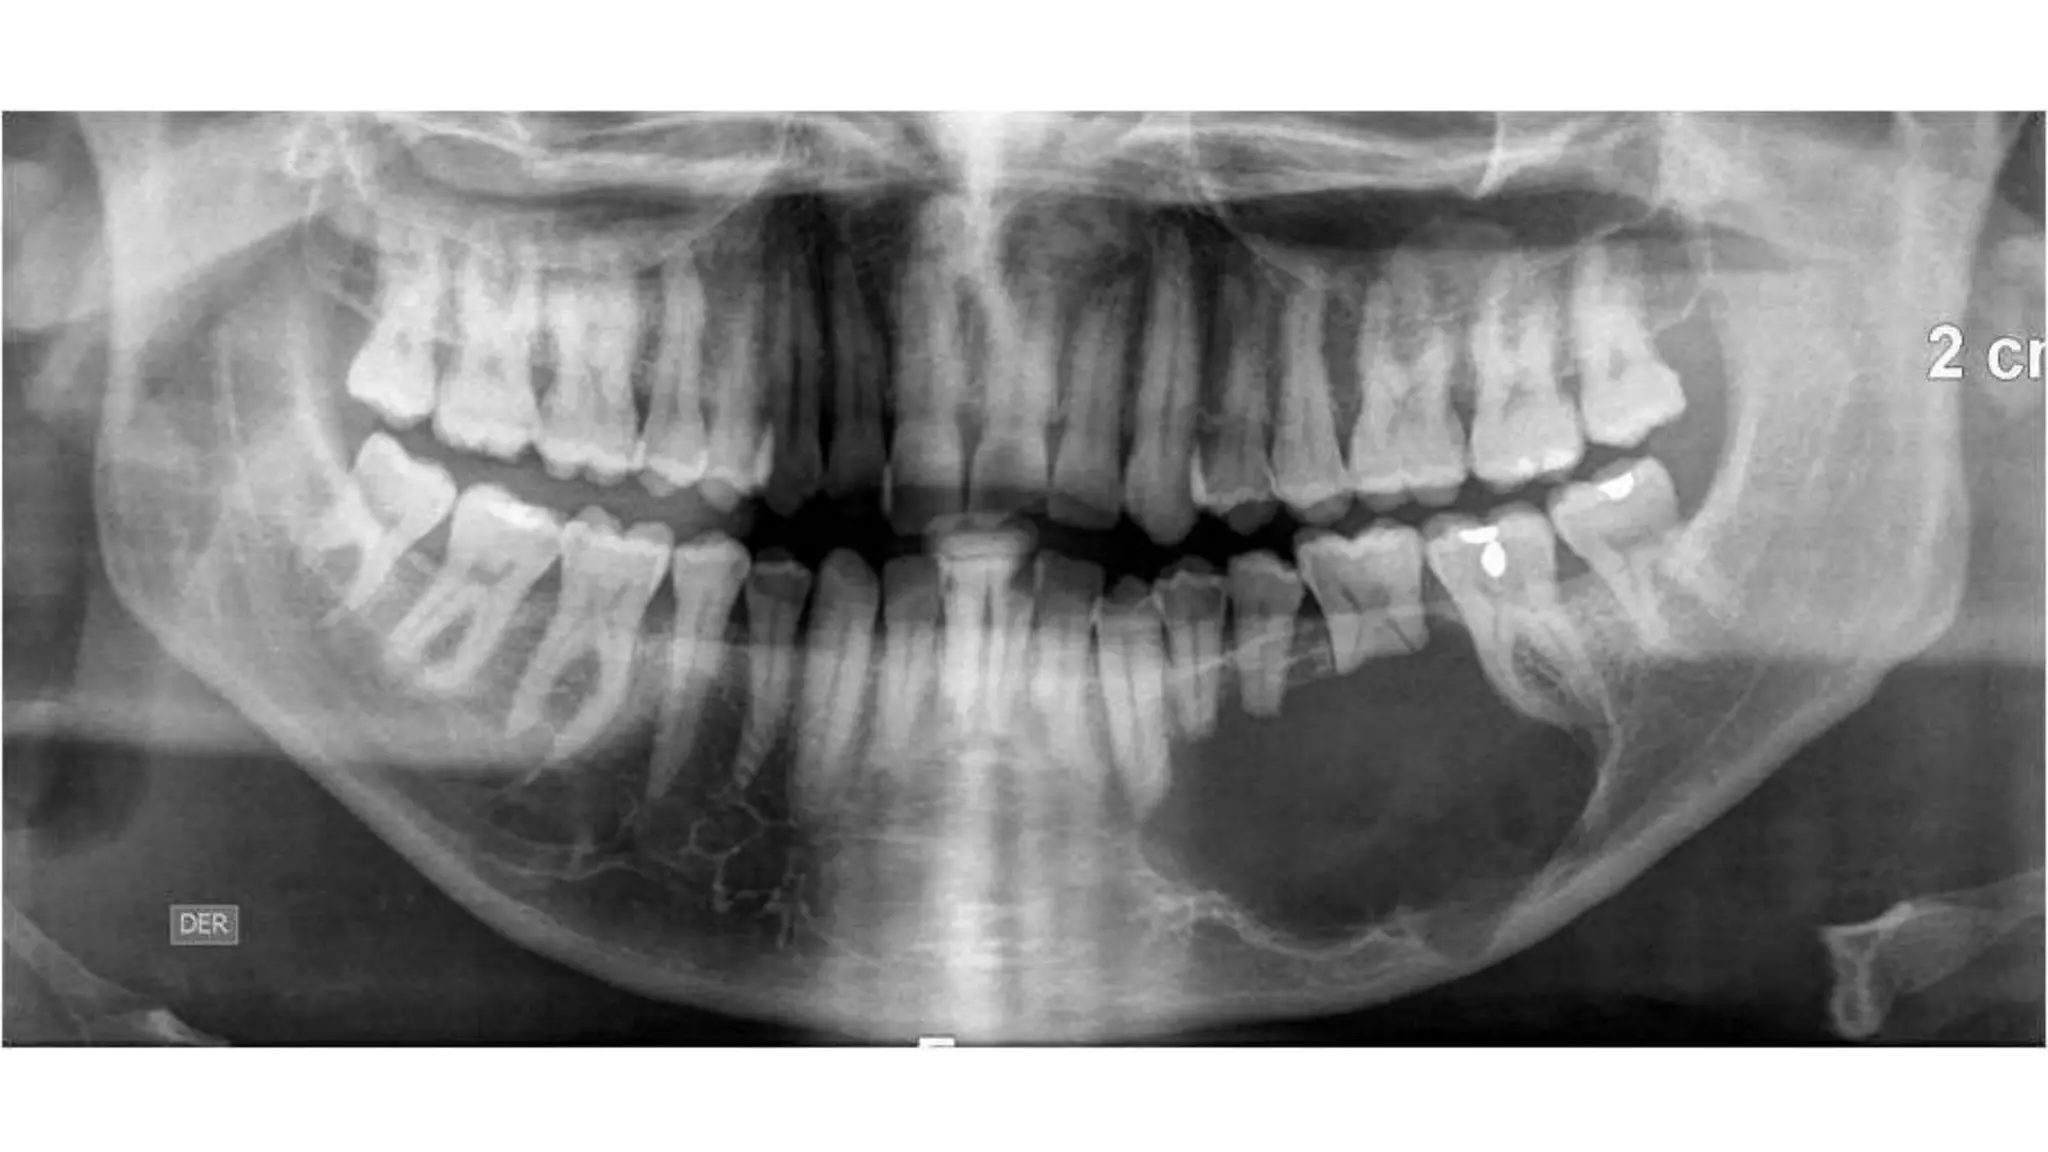

АМЕЛОБЛАСТОМА

Амелобластома – это доброкачественная одонтогенная опухоль челюстно-лицевой

локализации, вызывающая деструкцию костной ткани. По мере развития

амелобластомы возникает асимметрия лица, происходит постепенная деформация

челюсти, расшатывание и смещение зубного ряда

АМЕЛОБЛАСТОМА Амелобластома – этодоброкачественная одонтогенная опухоль челюстно-лицевой локализации, вызывающая деструкцию костной ткани. По мере развития амелобластомы возникает асимметрия лица, происходит постепенная деформация челюсти, расшатывание и смещение зубного ряда